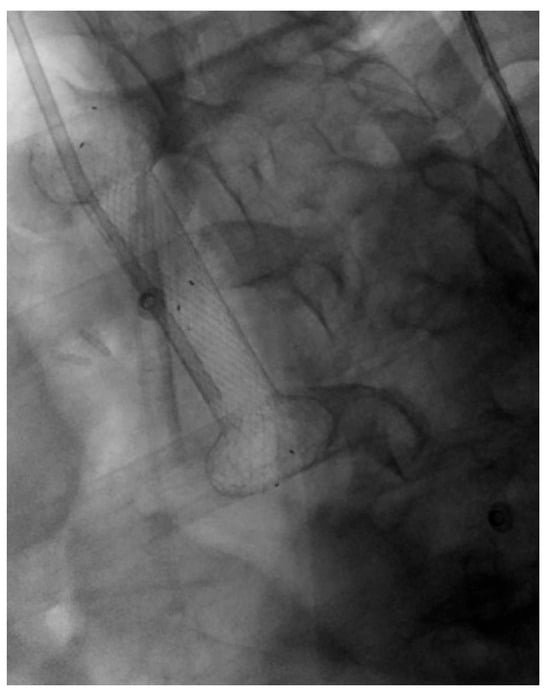

3.1.1. Role of Stent

Indications and Mechanism of Action

Efficacy and Adverse Events

3.2.1. Role of Stent